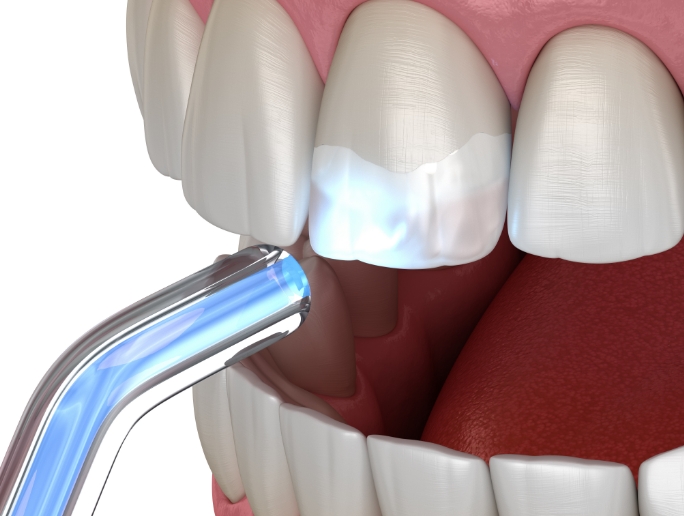

在通过锥形束CT精细确认智齿方向,

神经位置及与邻牙关系后,

仅在

确有必要的情况下才进行拔除

采用最大程度减少组

织损伤的方式来降低负担,

帮助患者更轻松地完成术后恢复